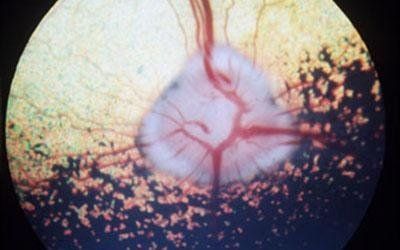

oftalmologia con chirurgia oftalmica a vicenza

L' oftalmologia veterinaria è una branca della medicina veterinaria che si concentra dalla cura degli occhi e la prevenzione delle malattie oculari. Al esame annuale fisico del soggetto viene valutata la salute degli occhi facendo controllo del occhio e dei anesi.

Se vengono rilevati problemi più gravi, come l'aumento della pressione oculare (glaucoma), cataratta, perdita della vista o problemi di secchezza oculare, sarà programmata una visita dal medico specialista, oftalmologo.

Alcune condizioni oftalmiche di interesse specialistico:

distacco della retina